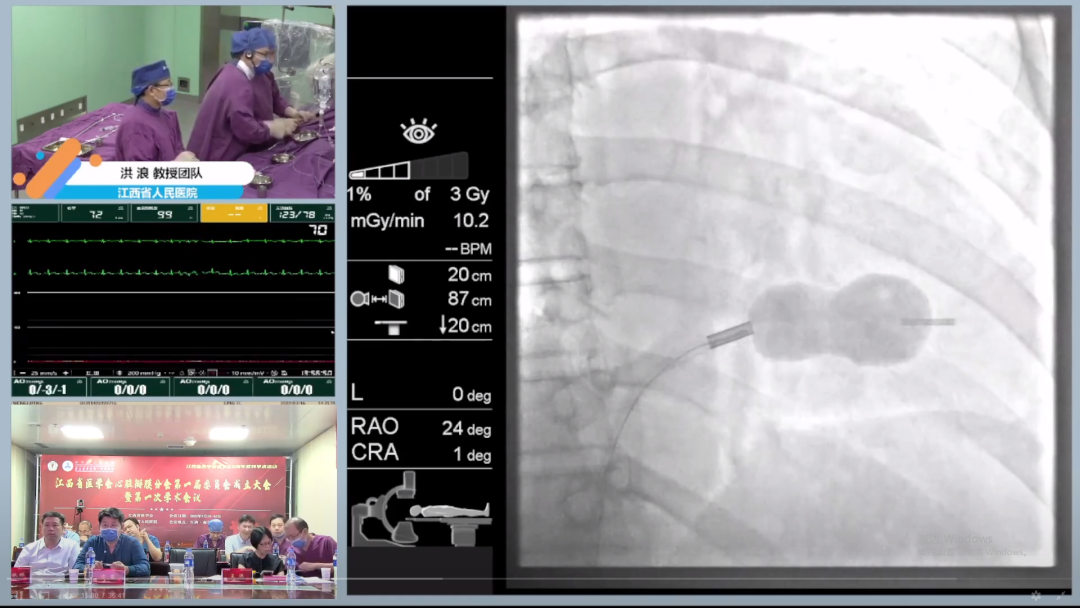

洪浪教授团队演示手术与参会嘉宾讨论手术策略

本次学术会议同步开设两个频道,主旨讲课与手术转播并举。在手术转播中,洪浪教授团队在线直播了包括主动脉瓣狭窄、主动脉瓣关闭不全、肺动脉瓣狭窄、二尖瓣狭窄在内的8台手术,实时与在线专家探讨手术策略,交流操作经验,复盘手术细节,手术均取得良好效果;除了在学术会议上进行手术演示,洪浪教授及团队早已将这项内容当作日常工作的一部分。